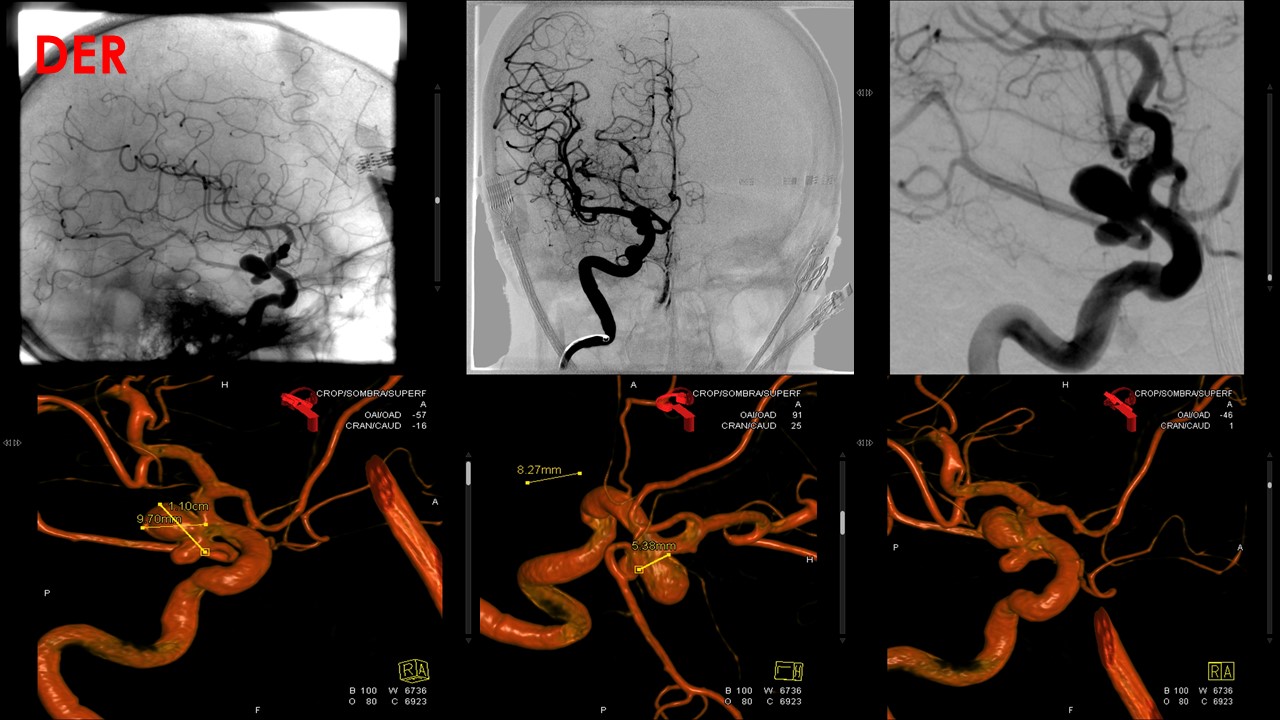

Procedimiento: Se realiza estudio diagnóstico confirmando la presencia de dos aneurismas localizado en

origen de comunicantes posteriores:

El derecho de 11x9x8mm con cuello de 5.3mm de morfología polilobulada, en su componente inferior se

origina la comunicante posterior.

Se realiza microcateterismo selectivo del saco aneurismático derecho, con protección de balón Transform,

el cual se ubica en carótida previo a la bifurcación, posteriormente se dispone en su interior un total de 15

coils. En la serie angiográfica de comprobación se identifica persistencia de mínimo saco residual con

permeabilidad de la comunicante.